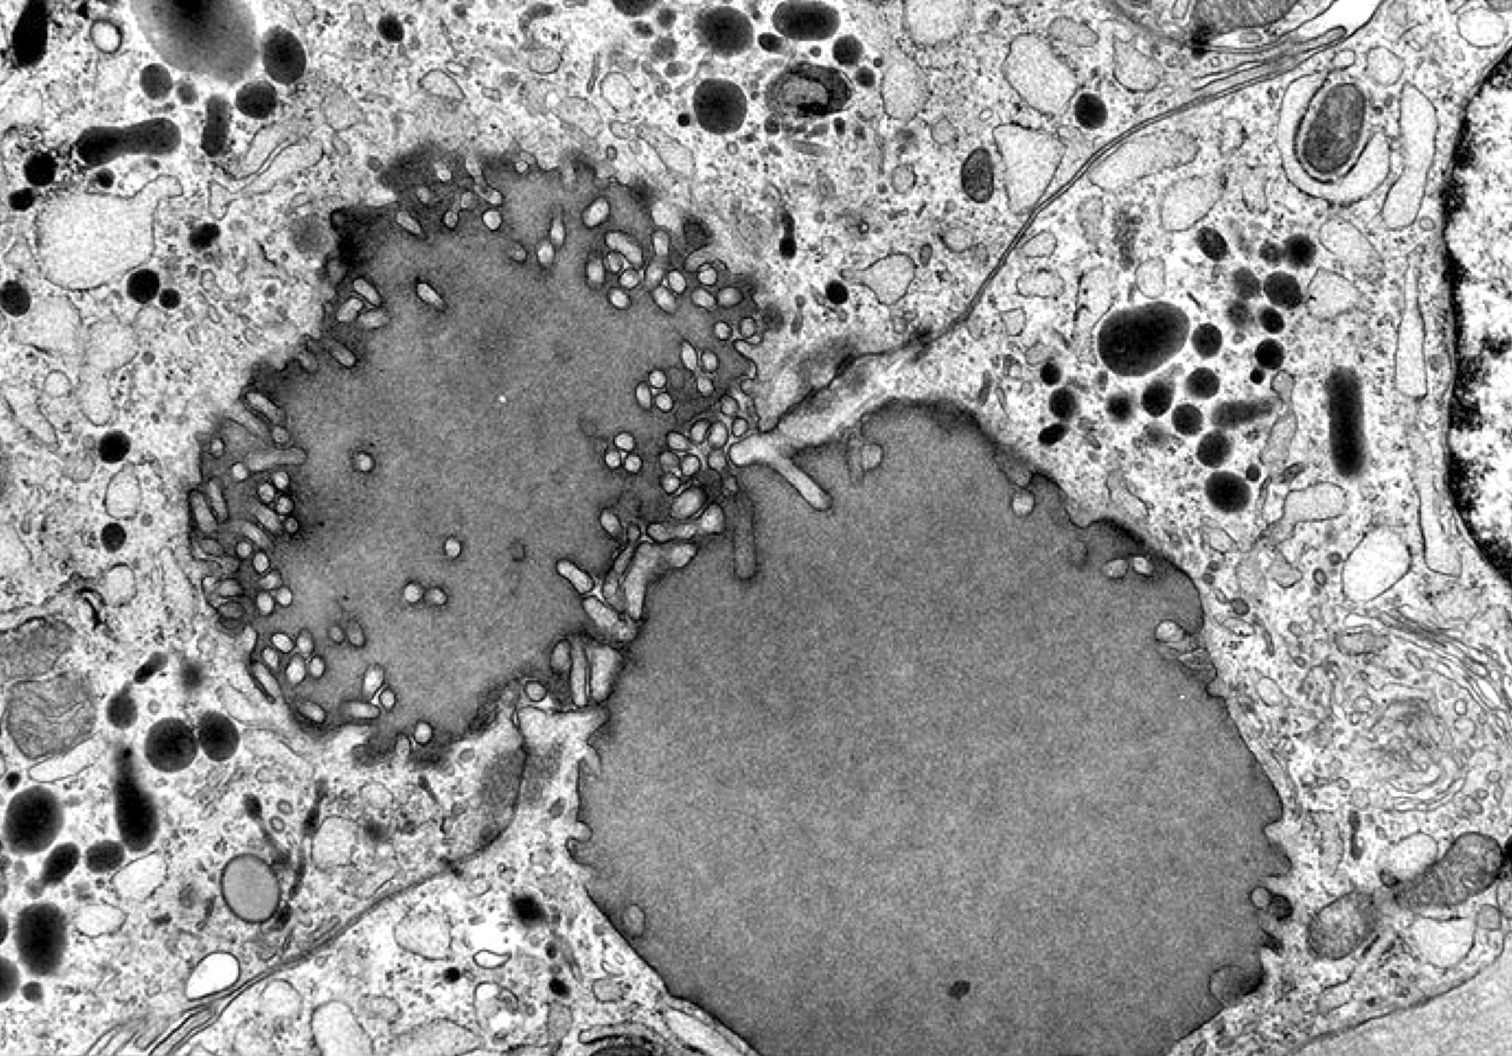

Electron microscopy description

- Similar to normal thyroid gland and hyperplastic nodules

- Hyperfunctioning follicular adenomas: organelle rich cytoplasm, especially rough endoplasmic reticulum; numerous, long microvilli on surface (Am J Clin Pathol 1982;78:299)

- Clear cell follicular adenomas: cytoplasmic vesicles of variable size; these may be dilated cisternae of the rough endoplasmic reticulum or mitochondria, lysosomes or endocytic vesicles (Virchows Arch A Pathol Anat Histol 1978;380:205)

Electron microscopy images